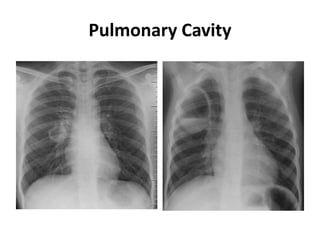

Pulmonary Cavity

• Carcinoma

• Autoimmune: Wegner

granulomatosis and

rheumatoid nodule

• Vascular: emboli (septic/bland)

• Infection/abscess: bacterial

(Klebsiella, Staphalococcus,

anareobic infections), fungal

(histoplasmosis), amebic,

hydatid cyst

• Trauma: pnematocele

• Young: congenital,

bronchogenic cyst